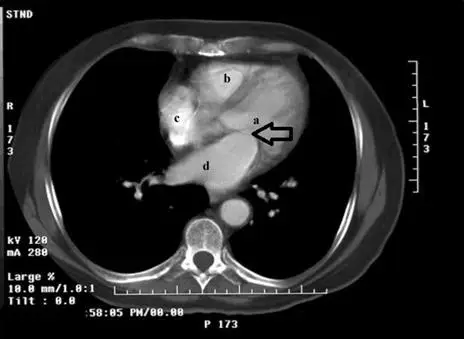

承上題【下圖 a、b、c、d所指最可能之解剖位置分別為何? 】附圖,箭號所指的解剖構造為何?

本題承接上題,在同一張胸部軸位增強 CT 影像中,辨識箭號所指的解剖構造。本題考查心臟瓣膜的解剖位置與影像辨識,特別是二尖瓣(mitral valve)的位置——位於左心房(left atrium, LA)與左心室(left ventricle, LV)之間的房室瓣。

影像中箭號(→)指向的位置:

- 箭號位於影像中央偏左,指向心臟中央的解剖結構,位於標記 a(左心室)的入口處

- 該位置處於左心房與左心室的交界處(atrioventricular junction),即房室瓣所在位置

- 對照上題答案:標記 a = 左心室,標記 d = 左心房。兩者之間的瓣膜即為二尖瓣(mitral valve)

- 箭號所指的構造處於左側心腔的房室開口(left atrioventricular orifice),是二尖瓣瓣葉結構所在

由此可判斷箭號指向二尖瓣(mitral valve)。